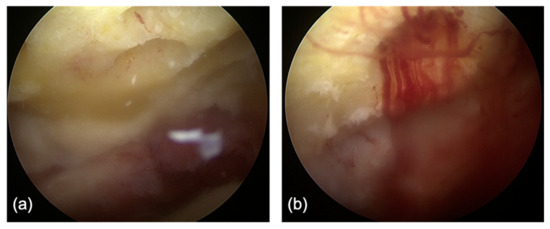

2.2. Surgical Technique